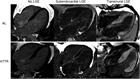

1. 造影MRIではextra-cellular volumeを算出でき、予後指標となることを追加した。